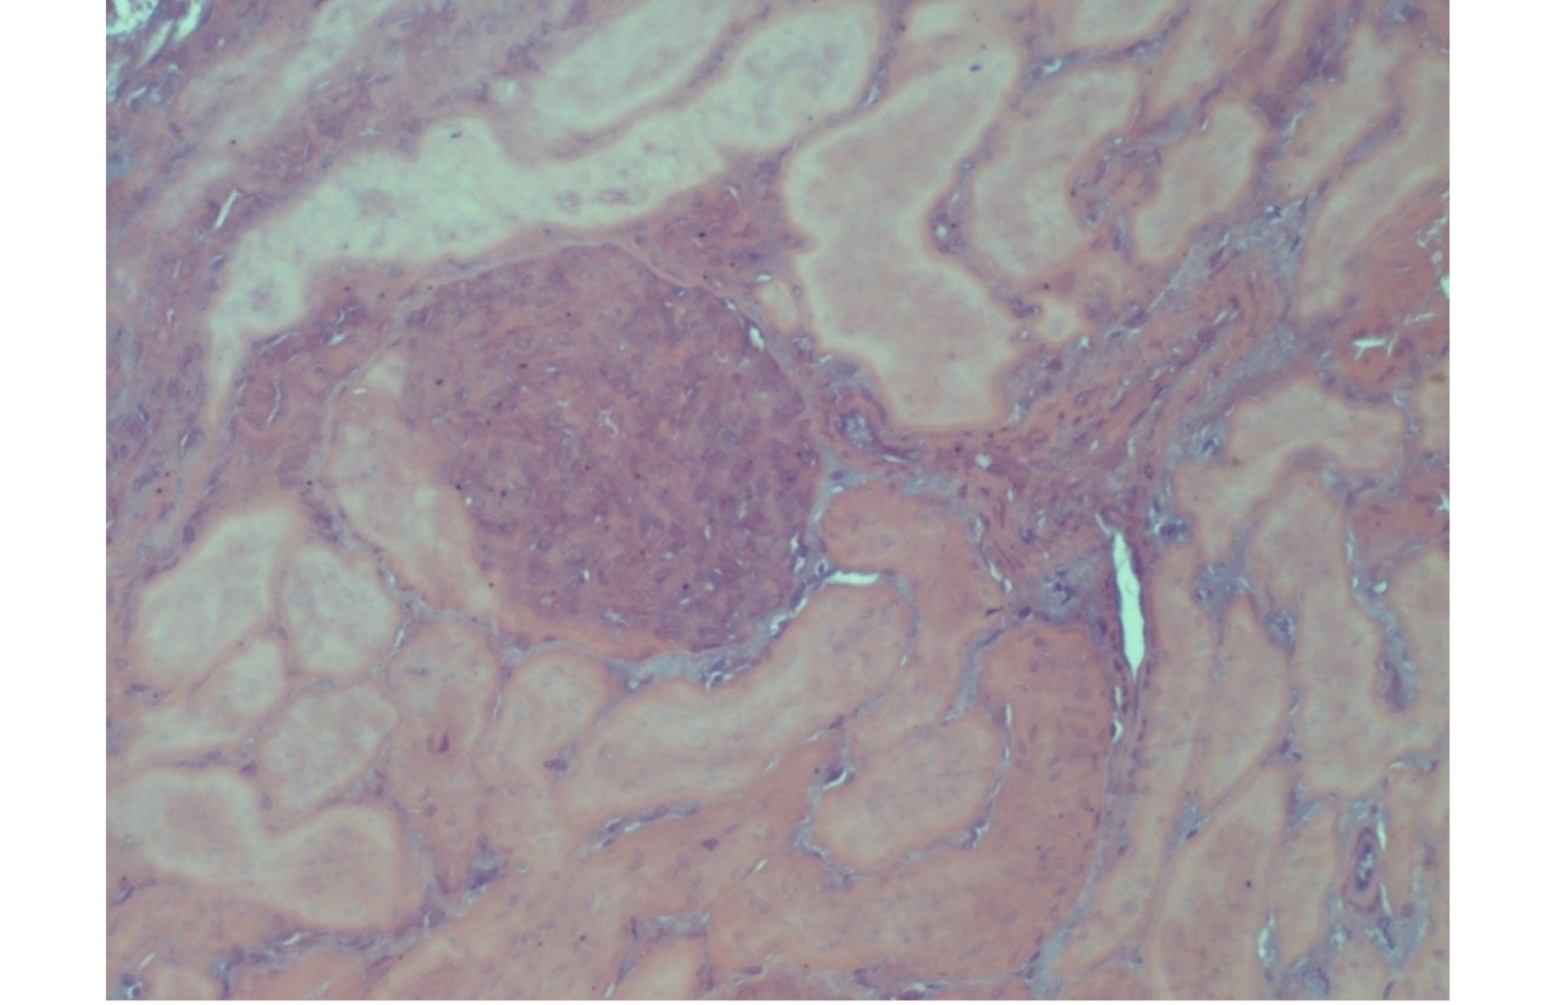

Histological lesions were observed in 19 kidney samples, all exclusively from group 1, with cadmium concentrations > 5.72 mg/kg w/w and from animals aged between 50 and 60 months. These samples exhibited the presence of neutrophils within the glomerular tufts and varying degrees of mesangial cell proliferation. Features consistent with obstruction typical of acute nephritic syndrome—progressing toward chronicity—were also observed. The glomerular capillary lumens appeared reduced, thereby compromising glomerular filtration (Figure 1).

Furthermore, evaluation of the histological kidney sections revealed marked proliferation of Bowman’s capsule cells, localized to part of the capsule’s circumference, forming the characteristic crescent-shaped structures. Tubulonephrosis and glomerulopathy were also evident (Figure 2).The progressive proliferation of the crescent led to obliteration of the glomerular tuft, resulting in irreversible destruction of the glomerulus and subsequent nephron atrophy (Figure 3). Additionally, perivascular sclerosis was observed in small- and medium-calibre arterial vessels (Figure 4).

Figure. 1. Kidney: obstruction of glomerular capillary lumina. HE (Hematoxilin Eosin) x 40.

Figure. 2. Kidney: great proliferation of Bowman’s capsule cells. Tubulonephrosis and glomerulopathy HE (Hematoxilin Eosin) x 20.

Figure. 3. Kidney: nephron atrophy and progressive tubule interstitial glomerular-nephritis. HE (Hematoxilin Eosin) x 20.

Figure. 4. Kidney: perivascular sclerosis in the small and medium-calibre arterial vessels. HE (Hematoxilin Eosin) x 10.